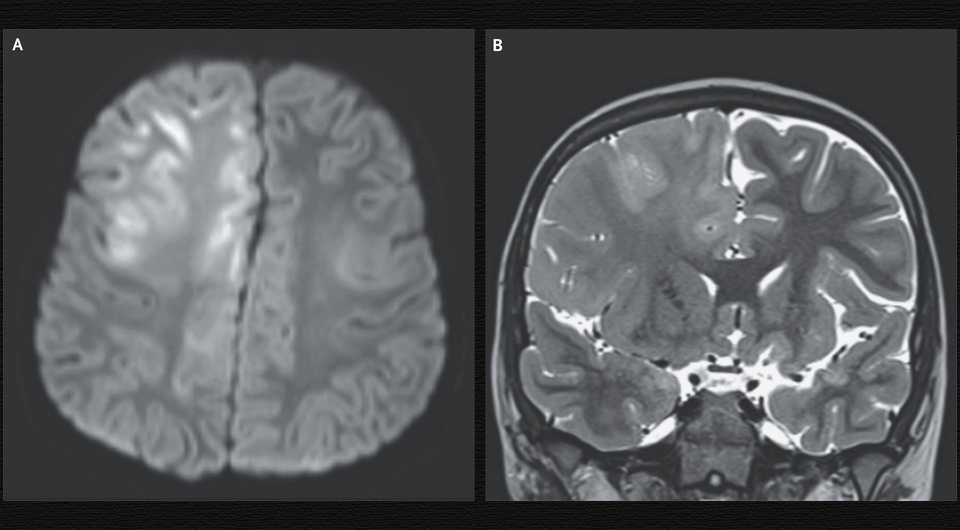

В американскую клинику третичной медицинской помощи поступил семилетний мальчик с когнитивным дефицитом и судорогами на протяжении трех месяцев. В возрасте семи месяцев он заразился корью во время проживания в Афганистане, где эта инфекция эндемична. При осмотре наблюдались неспособность говорить, диффузная гиперрефлексия и клонические судороги. На МРТ головы визуализировались отек и ограниченная диффузия в лобных долях мозга, которые охватывали кору и белое вещество и распространялись в мозолистое тело. На электроэнцефалограмме с обеих сторон определялись комплексы Радермекера — синхронные симметричные высокоамплитудные периодические разряды. Врачи Майкл Кунг (Michael Kung) и Джон Росс Кроуфорд (John Ross Crawford) из Калифорнийского университета в Ирвайне описали этот случай в The New England Journal of Medicine.

Анализ спинномозговой жидкости выявил повышенный уровень общего иммуноглобулина G и оптическую плотность специфичного к кори иммуноглобулина G при иммуноферментном анализе 20,8 (при норме менее 1,1). Несмотря на атипичную МРТ-картину, мальчику поставили диагноз подострого склерозирующего панэнцефалита на основании анамнеза, результатов ЭЭГ и анализа спинномозговой жидкости. Это крайне тяжелое осложнение персистирующей инфекции вирусом кори представляет собой прогрессирующее нейровоспаление и нейродегенерацию. Оно может развиться через годы после острой инфекции и практически всегда летально, вакцинация тем не менее обеспечивает хороший профилактический эффект. Пациент скончался через год после появления первых симптомов.